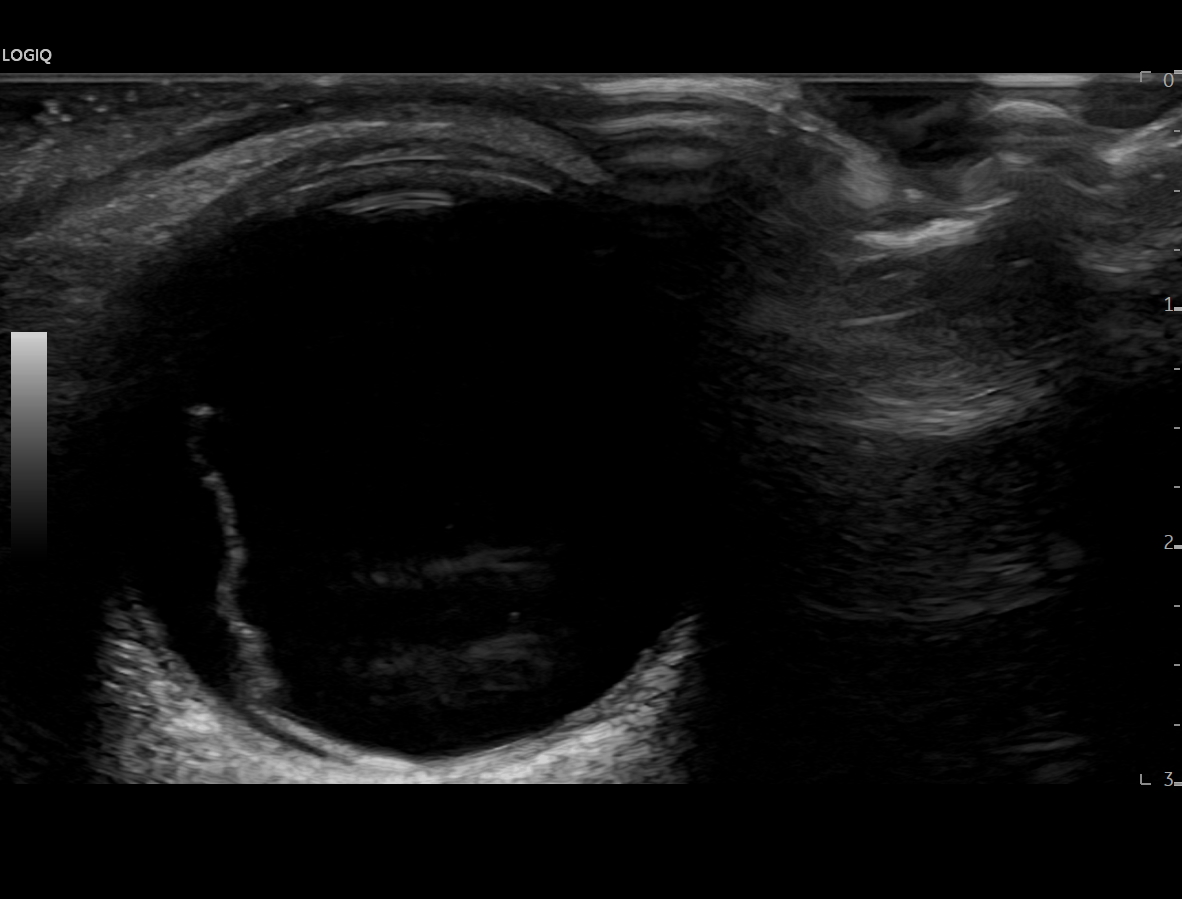

En urgencias hospitalarias se valora presión intraocular de ojo derecho en 12 mmHg y se realiza ecografía clínica del ojo con sonda plana, apreciando la imagen de sospecha de desprendimiento de vítreo posterior al apreciar una capa flotante en la porción posterior del mismo que en condiciones normales, no debería visualizarse.

Dado que la paciente no tiene antecedentes personales ni factores de riesgo cardiovascular, no parece corresponderse con una degeneración macular ni un desprendimiento de retina, aunque sí parece impresionar de un desprendimiento de vítreo posterior como posible causa inicial.